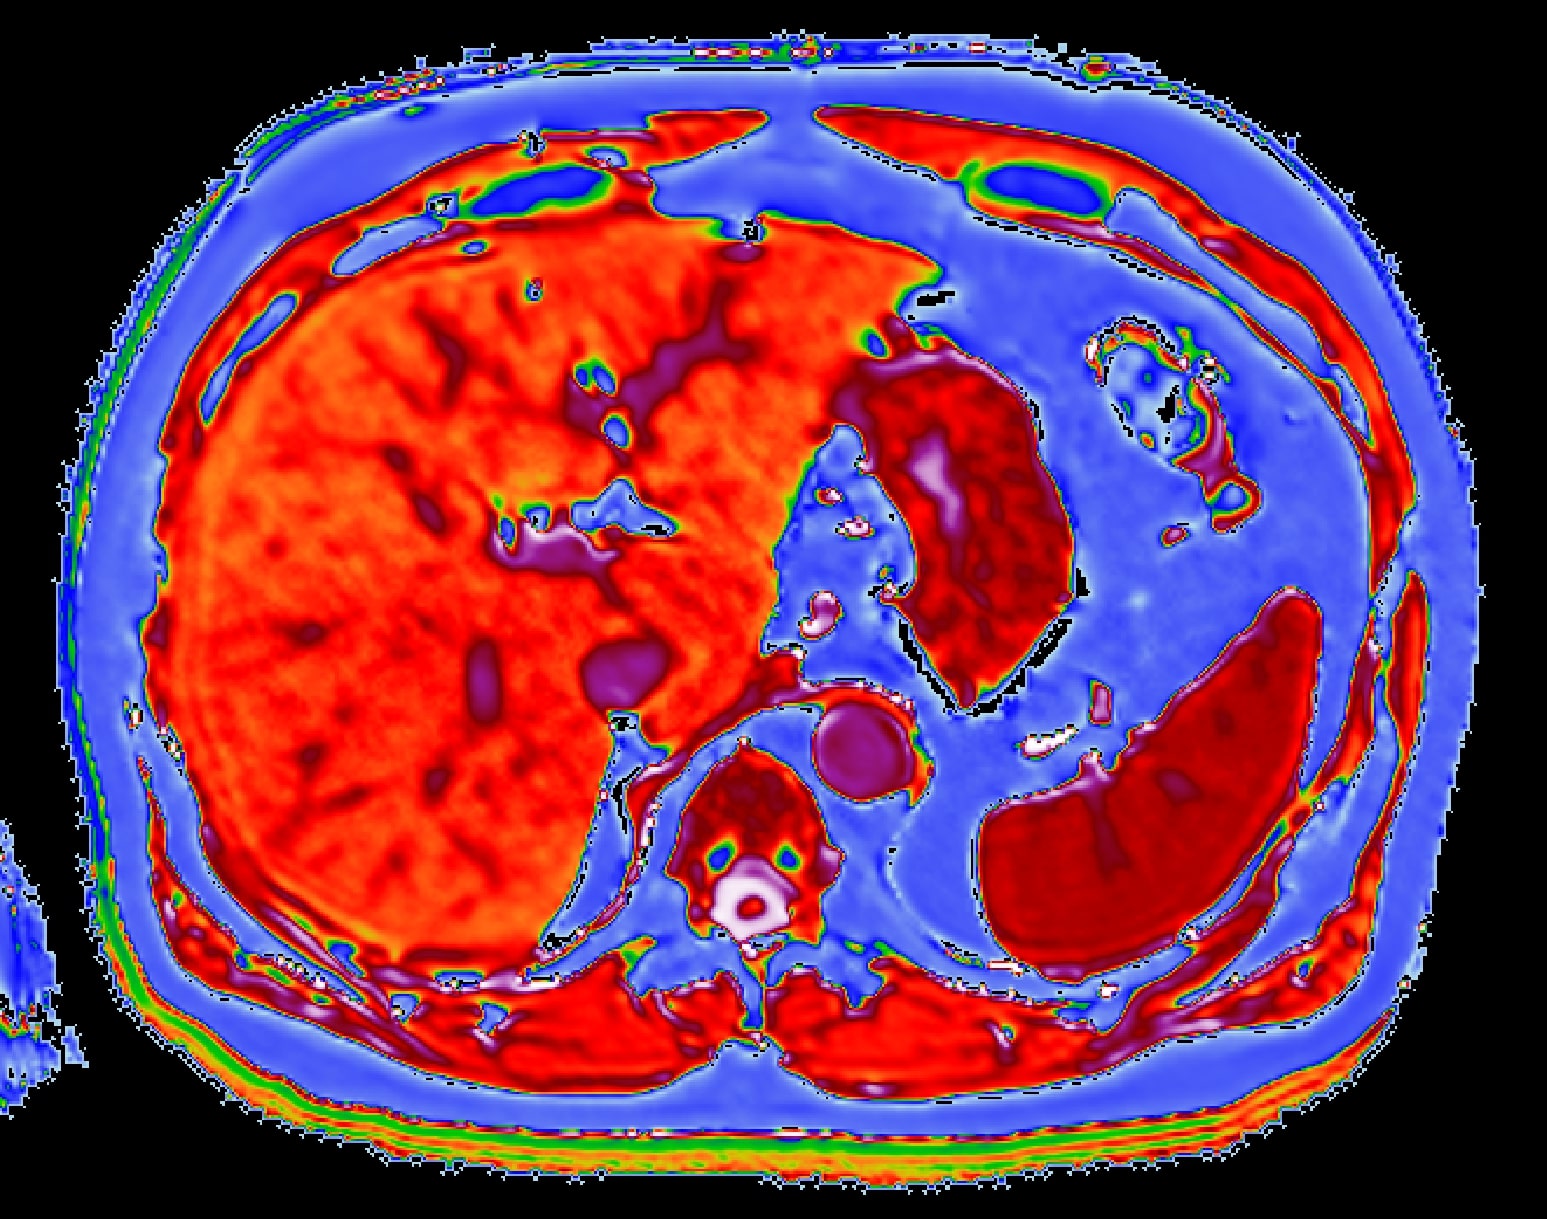

LiverMultiScan is a test that combines digital image processing and trained experts to quantify and characterise tissue from an MRI scan of the liver, giving doctors reliable information about the health of the whole liver. It can be used with modern MRI scanners, so no new hardware is needed. It is approved for use across Europe to aid diagnosis of liver disorders and abnormalities.

LiverMultiScan is FDA 510(k) cleared in the U.S. and CE marked by notified body BSI 0086 in Europe. It enables non- invasive and quantitative liver tissue characterisation to quickly and consistently quantify liver fat, as well as biomarkers which have been shown to correlate with iron and fibro-inflammation. It is a rapid and scalable technology that can be seamlessly integrated into existing MR examinations, without the need for contrast agent.

- Patients undergo an MRI scan on a compatible scanner – this takes less than 15 mins and no contrast agent is required.

- The scans are sent electronically to a secure reporting laboratory to be quantified using a proprietary algorithm. The results are processed by clinical and imaging specialists.

- The report is usually sent back to the referring doctor within 24 hours. It provides summary values of three biochemical characteristics of the liver as well as images that depict the health of the whole organ.